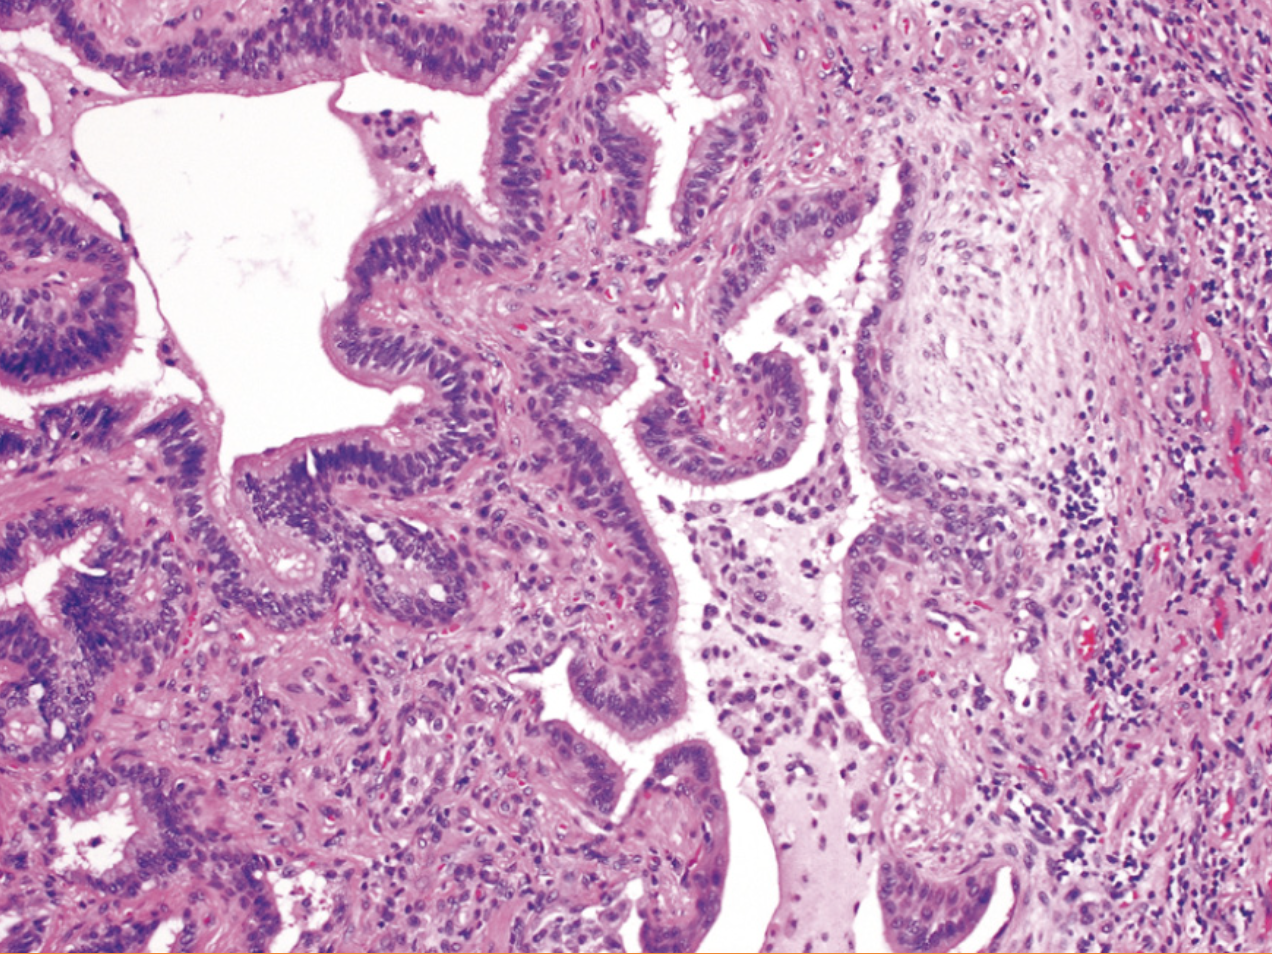

FPI microscópicamente

Fibrosis intersticial parcheada que varía de intensidad y antigüedad

¿Qué es?

Neumonía intersticial

Neumonía intersticial usual, ¿qué se encuentra a la izquierda?

Patrón en panal de abeja

¿Qué contienen las lesiones iniciales de la FPI?

Proliferación exuberante de fibroblastos (focos fibroblasticos)

¿A qué se le denomina fibrosis en panal de abeja?

Espacios quísticos revestidos por neumocitos tipo II hiperplásicos o epitelio bronuiolar

¿Qué tipo de inflamación hay en la fibrosis pulmonar idiopática?

Inflamación leve o moderada dentro del tejido fibrótico